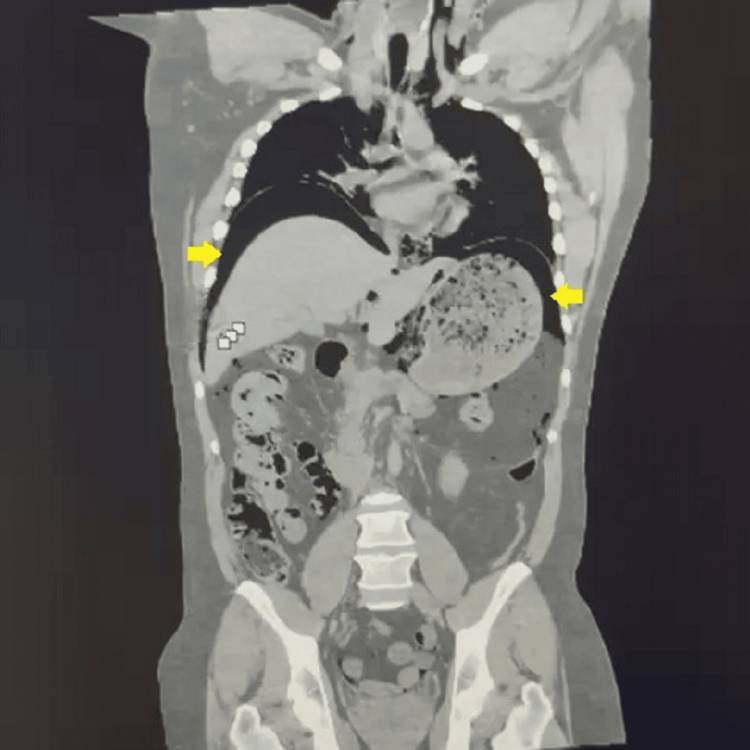

National Library of MedicineA CT scan of the patient’s stomach.

A CT scan confirmed their suspicions, and they were able to identify a layer of trapped nitrogen in the patient’s abdomen, confirming the gas had ruptured his stomach.